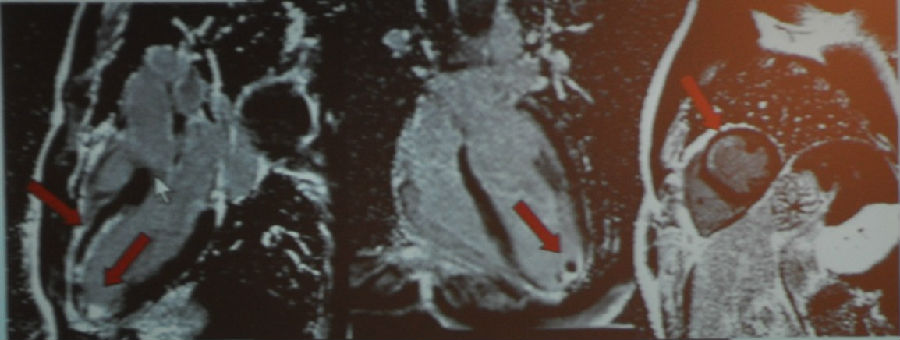

图5 MR成像(LVEF=48%,左室质量159g/m2)

严重的向心性肥厚,心壁厚度2.4cm(正常值<1.2cm)。可以看到周围白色的区域是心包积液,至少是中度的。此外尚有右心严重肥厚,厚度>1cm。

图6 MR增强(从左到右依次为四腔心切面、短轴切面)

刚才已经讲过黑色部分是正常的心肌组织,那么我们可以从该患者的MR增强图中看到整个心脏都是重度弥散性的增强,已经没有正常的心肌组织了。

图7 T1加权像

图8-9 左:增强图像 右:刚果红染色

我们接着进一步做了定量检查,最终患者被诊断为心脏淀粉样变。这样的疾病在临床上是比较难以诊断的,除非做活检。最终这名患者还是做了活检。这类疾病的确诊对患者治疗方案的制定是有明显的指导作用的,患者后续可以针对淀粉样变做进一步的治疗而不是单纯地只治疗心衰。